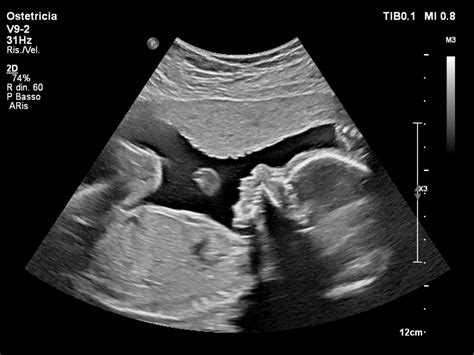

Le Misure Ecografiche: Dalla Testa al Femore

Il Diametro Biparietale (BDP) corrisponde alla misura trasversale del cranio fetale. La Circonferenza Cranica (CC) è la misura del perimetro della testa. La Circonferenza Addominale (AC) è la misura del perimetro dell'addome. La Lunghezza del Femore (FL) è la misura dell'osso della coscia. La Lunghezza dell'Omero (HL) è la misura dell'osso del braccio.

Queste misure vengono poi inserite in formule specifiche o confrontate con tabelle di riferimento per stimare il peso fetale e la sua crescita. È importante notare che la proporzione tra le diverse misure può essere altrettanto significativa quanto le misure assolute. Ad esempio, una testa e un addome grandi rispetto alla lunghezza del femore potrebbero destare preoccupazione, ma è fondamentale considerare l'andamento generale della crescita e le caratteristiche genetiche dei genitori.